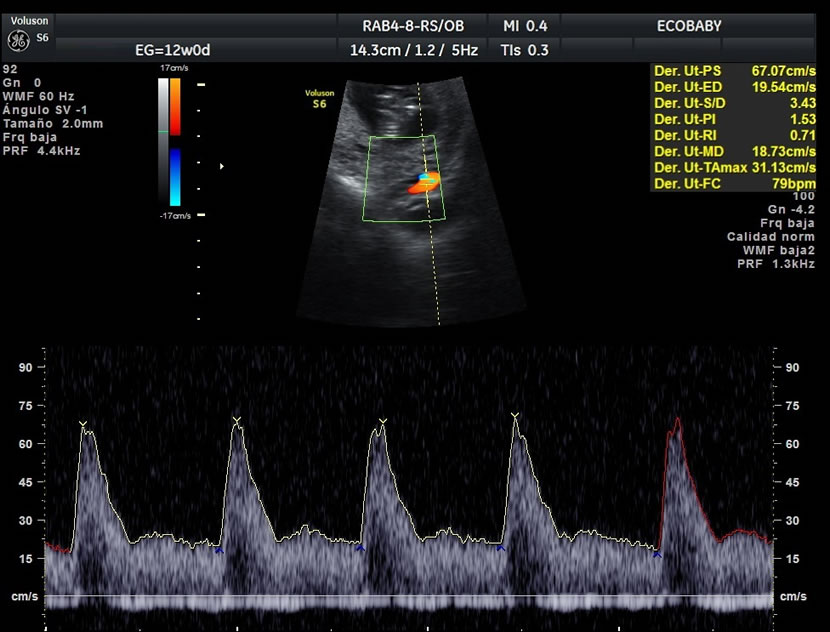

> Para estudiar el flujo a través de la válvula tricúspide del corazón fetal y el ductus venoso